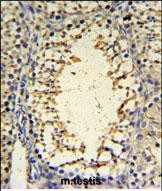

IHC 1/100-1/500 Human,Mouse,Rat

The IMP3 antibody is a critical tool in research and diagnostics, enabling detection of IMP3 protein overexpression in tumor tissues via immunohistochemistry (IHC) or Western blot. Elevated IMP3 levels correlate with poor prognosis, metastasis, and resistance to therapy, making it a potential biomarker for cancer progression. Additionally, IMP3 antibodies help study molecular mechanisms, such as its interaction with oncogenic mRNAs (e.g., IGF2. MYC) or signaling pathways (e.g., Wnt, KRAS), providing insights into tumorigenesis.